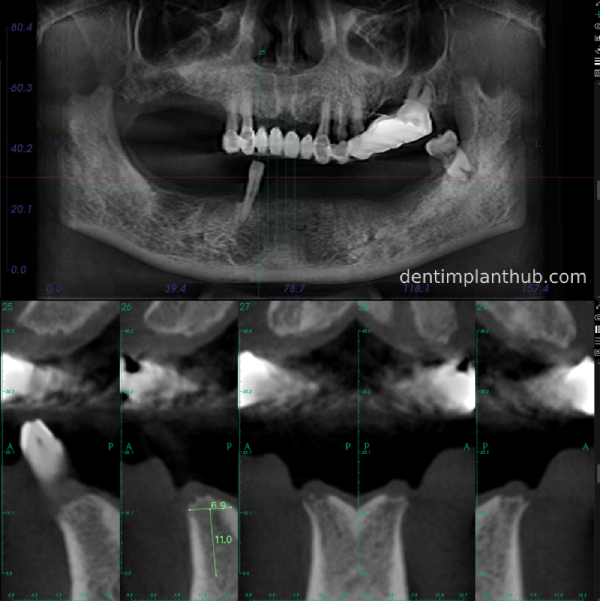

A review of the CBCT on 6/10/23 was more promising and a surgical plan was subsequently drawn up.

46

44

42

32

34

36

General schematic of the surgical programme

Detailed list of implant types and composite abutments to be prepared.

46 tooth position, implant model number 4810, RC series straight composite abutment;

44 tooth position, implant model number 4110, RC series straight composite abutment;

42 tooth position, implant model number 4110, RC series straight composite abutment; alternate implant model number 3310, alternate NC series straight composite abutment;

32 tooth position, implant model number 4110, RC series straight composite abutment; alternate implant model number 3310,. Alternate NC Series Straight Composite Abutment;

34 Dental Position, Implant Model No. 4110, RC Series Straight Composite Abutment;

36 Dental Position, Implant Model No. 4808, RC Series Straight Composite Abutment;